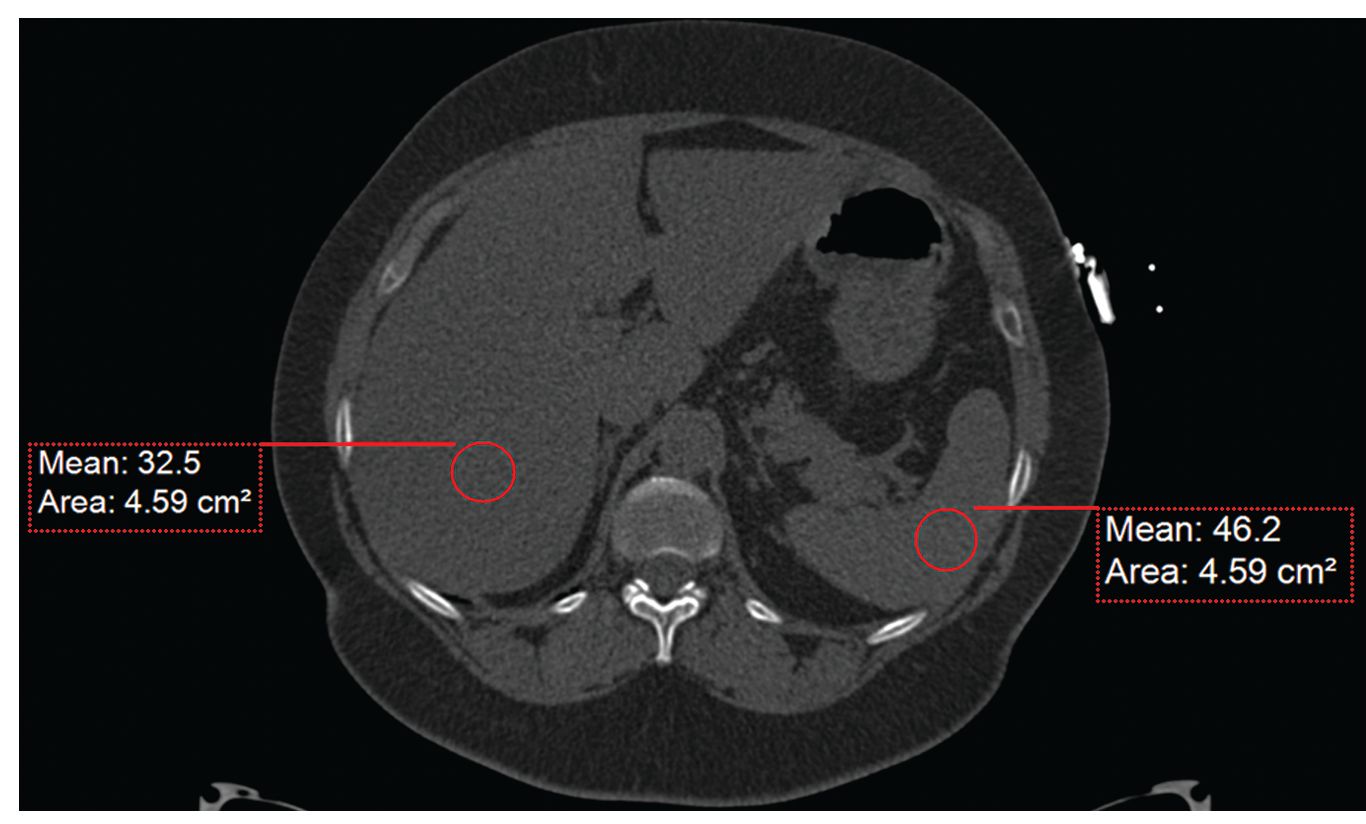

Case History: Female patient in early 60s with abdominal pain and nausea.